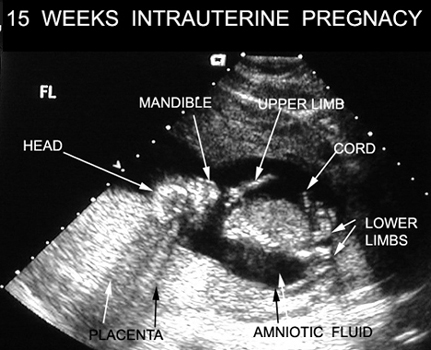

15 Weeks Intrauterine Pregnancy |

|